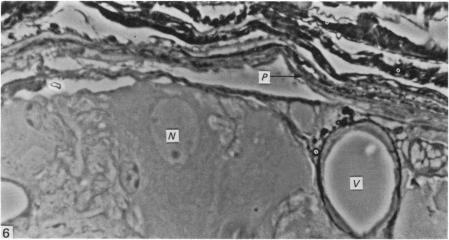

Horseradish peroxidase (HRP) was applied to the capsules of various autonomic ganglia in vivo. The capsules of the inferior mesenteric ganglion and superior cervical ganglion of guinea-pigs and the inferior mesenteric ganglion of mice were readily penetrated by the enzyme. The capsule of the mouse superior cervical ganglion was apparently impermeable to HRP, while that of the guinea-pig lumbar sympathetic trunk was intermediate in permeability, being most readily penetrated by HRP around the blood vessels entering or leaving the ganglia. The results of retrograde transport experiments from the guinea-pig inferior mesenteric ganglion to spinal ganglia are considered in the light of the ready permeability of its capsule.

将辣根过氧化物酶(HRP)应用于体内各种自主神经节的被膜。豚鼠肠系膜下神经节和颈上神经节以及小鼠肠系膜下神经节的被膜很容易被该酶穿透。小鼠颈上神经节的被膜显然对HRP不可渗透,而豚鼠腰交感干的被膜通透性介于两者之间,在进出神经节的血管周围最容易被HRP穿透。根据豚鼠肠系膜下神经节被膜的易通透性,考虑了从该神经节到脊髓神经节的逆行运输实验结果。